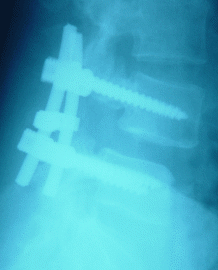

26-APRIL-2007 HANAA KHADER ABBAS 46 YEARS POSTDISCECTOMY III DEGREE SPONDYLOLISTHESIS L4-5 WITH AGONIZING SCIATICA AND WEAK BOTH FEET.

The patient came to the clinic 23-April with agonizing bilateral sciatica and severe weak both feet with inability to walk more than 100 meters.

The patient was operated elsewhere 22-May-2006 for PLD L4-5 with subsequent deterioration of her condition.

MRI done 26-January-2007 with LSS X-ray confirmed the presence of III degree spondylolisthesis L4-5 with complete absence of the isthmi.

On examination: the patient had exaggerated scoliotic stance with SLRS 40 degrees both sides with more pain in the right. The right foot dorsi and planterflexion were 3/5 and the left 4/5. There was hypalgesia of the right L5 and S1 territories.

Skeletonization of the lateral masses of L5-S1 both sides and the L4-5 respectively. There were no lateral masses. The transverse processii were identified and using transpedicular screws 45 mm length and 7.5 mm width with 2 polyaxial type in the upper side and monoaxial in the lower part, transpedicular screw fixation was performed with distraction-reduction with bridge inserted between the 2 rods.

Smooth postoperative recovery with normalization of the power of both feet.

Postoperative Lateral LSS X-ray         Postoperative LSS X-ray AP-view